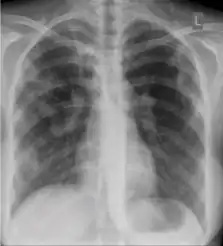

Chest X-ray

Tuberculosis creates cavities visible in x-rays like this one in the patient's right upper lobe.

A posterior-anterior (PA) chest X-ray is the standard view used; other views (lateral or lordotic) or CT scans may be necessary.

In active pulmonary TB, infiltrates or consolidations and/or cavities are often seen in the upper lungs with or without mediastinal or hilar lymphadenopathy.[1] However, lesions may appear anywhere in the lungs. In HIV and other immunosuppressed persons, any abnormality may indicate TB or the chest X-ray may even appear entirely normal.[1]